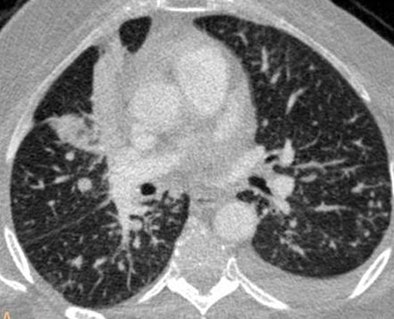

| Axial image shows an area of consolidation in the middle lobe, multiple bilateral small nodules, and left pleural effusion. No filling defects are seen in the pulmonary arteries. |

Collateral findings in patients with PE included pleural effusion (n = 27), parenchymal consolidation (n = 15), and tumors (n = 7). In 165 scans that were negative for PE, 75 patients had no significant findings at CT and 90 had pleural effusion (n = 66), parenchymal consolidation (n = 36), or tumors (n = 10).

"Even in a population with a prevalence of PE that is similar to or slightly higher than what is reported in the literature, most of the exams we are going to perform will not have PE -- but MDCT allows us to have a concurrent or alternative diagnosis," she said.